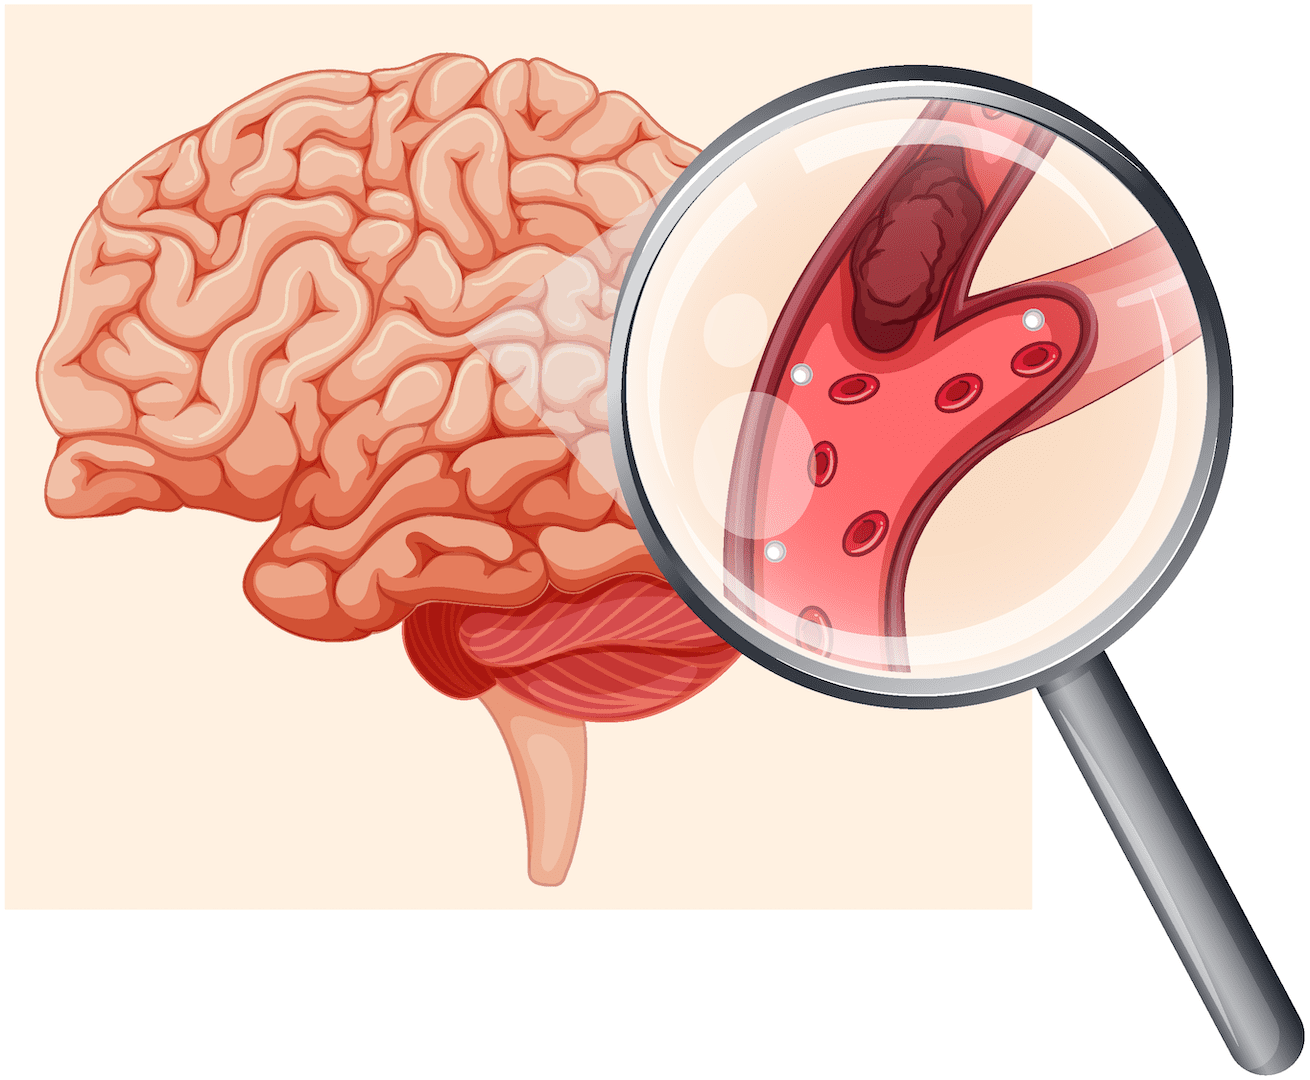

मस्तिष्कघात र ब्रेन हेमोरेज : जब उनको एक्कासी देब्रे हातखुट्टा चलेन र बोली पनि बन्द भयो…

सोमबार, कात्तिक १३, २०८०ट्रेन्डिङ